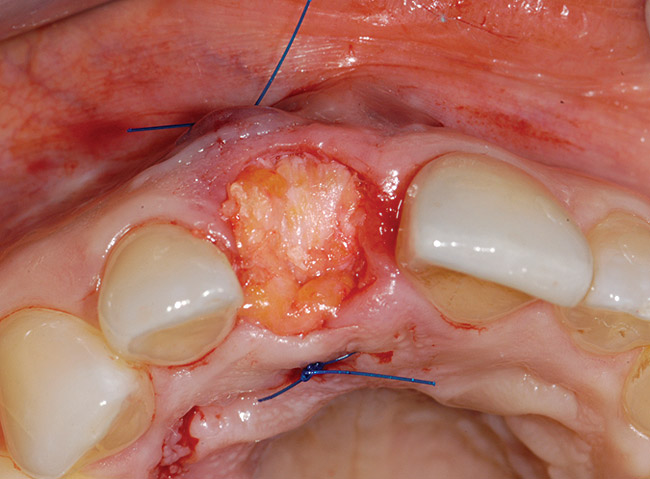

Case 3: Treatment Strategy for Severe Tissue Degradation (Labial Plate Loss)

A 39-year-old woman presented with a failing endodontically treated maxillary right central incisor. Clinical and radiographic examination revealed a thick, flat periodontal biotype, high smile line, and a fistulous tract of the labial vestibule opposite the incisor (Figure 16 and Figure 17). Also noted post-extraction was a thin (< 2 mm) labial plate with 8 mm of vertical bone loss (Figure 18). Treatment consisted of a conservative flapless extraction with placement of a free connective tissue graft (Figure 19) sutured through the socket, along with placement of a bone mineralized allograft (MinerOss) (Figure 20 and Figure 21). Five months post-extraction, a root-form implant was placed, nonsubmerged, along with a bovine bone xenograft as a veneer into a sub-periosteal labial pouch (Figure 22 through Figure 24). A provisional crown was placed 3 months later, allowing for adequate soft-tissue grooming (Figure 25).

Figure 18  Post-extraction socket defect with loss of labial plate.

Figure 18

Figure 19  Connective tissue graft introduced via extraction socket.

Figure 19

Figure 20  Socket grafted with mineralized irradiated bone allograft.

Figure 20

Figure 21  Completed socket graft with connective tissue graft.